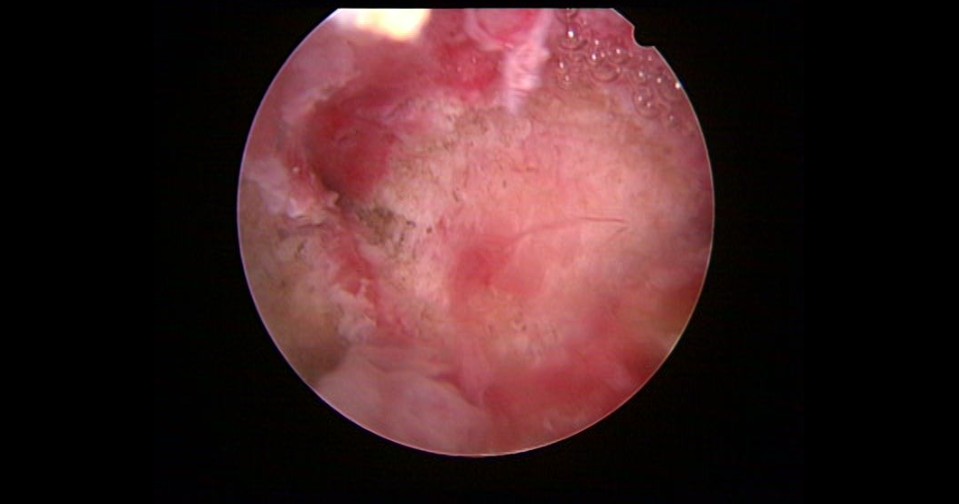

患者32岁,G6P0,继发不孕,2017年8月行宫腔镜探查,发现宫腔两侧及宫底致密粘连,尤其是宫腔右侧多重粘连,宫腔狭小。单极电切分粘,恢复宫腔形态,显露双侧输卵管开口。2018年8月自然妊娠40多天,我在兰州大学附一院生殖中心进修,病人微信发B超给我,大孕囊,胎心微弱,外院疑诊胚胎停育,拟行清宫,嘱病人不要轻易清宫,继续保胎1周,复查B超,胚胎发育正常。病人的信心和坚持成就了她自己和孩子的奇迹,孕期顺利,足月分娩。后病人再次妊娠1次,人流终止妊娠,现41岁,G8P1。